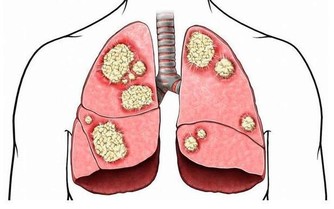

除此之外,冠心病等心血管疾病、各種慢性疾病都會在這個時期爆發,

因此很多人認為這段時間也是“疾病高發期”。